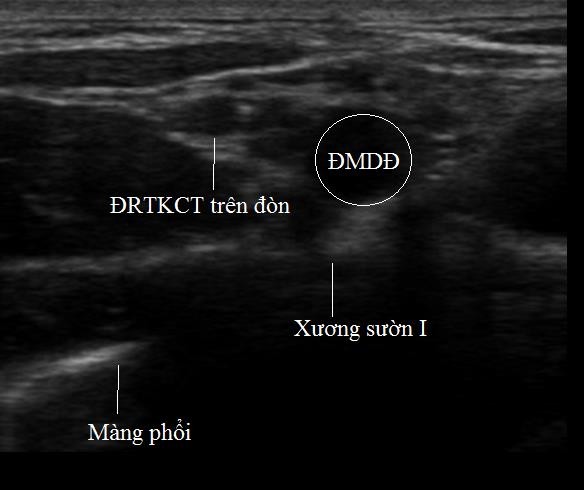

*Tìm ĐRTKCT và xương sườn I:

- Nằm ngoài và nông hơn so với ĐM dưới đòn

- ĐRTKCT xuất hiện là một đám cấu trúc vòng tròn tăng âm xung quanh, giảm âm vùng trung tâm.

Xương sườn I: Hình tăng âm có bóng cản phía sau.